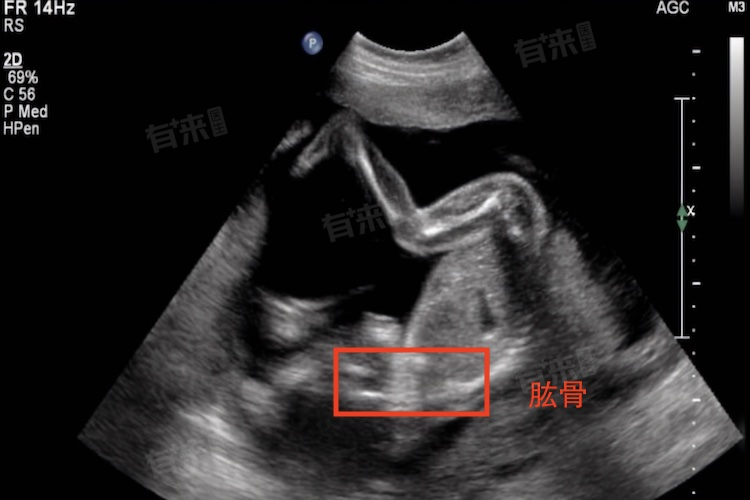

- HL主要通过超声检查进行测量,在孕妇进行产检时,医生会使用超声探头在孕妇腹部进行扫描,通过图像显示胎儿的肱骨,并测量其长度。这种测量方法无创、安全且准确度高。

- HL的正常值范围会根据胎儿的孕周而有所不同,一般来说,随着孕周的增加,胎儿的肱骨长度也会逐渐增长,医生会根据具体的孕周和超声检查结果来判断胎儿的肱骨长度是否在正常范围内。